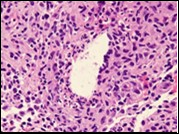

Core needle biopsy of idiopathic granulomatous mastitis enunciates multiple aggregates of non- caseating epitheloid cell granulomas within and encompassing breast lobules, constituted of epitheloid histiocytes, lymphocytes, neutrophils and multinucleated giant cells. Granulomatous inflammation is predominantly lobulo-centric. The inflammation is preponderantly composed of lymphocytes, plasma cells, epitheloid histiocytes, multinucleated giant cells and neutrophils. Neutrophils can configure micro-abscesses and encompass vacant micro-cystic cavities, morphological features which are in common with cystic neutrophilic granulomatous mastitis. Non specific lobulitis along with a lymphoid and plasma cell infiltrate accompanies the granulomatous inflammation. Necrosis is usually absent. Neutrophilic micro-abscesses can be accompanied by fistula formation 4, 5.

Multinucleated giant cells are detected in an estimated three fourths (78.5%) instances. Plasma cells are discernible in around half (53.9%) of the subjects and usually appear at the margins of cystic vacuoles with centric accumulation of neutrophils within the granulomas.

Figure 1.Granulomatous mastitis with the configuration of epitheloid cell granuloma and a lymphoid and plasma cell infiltrate9.